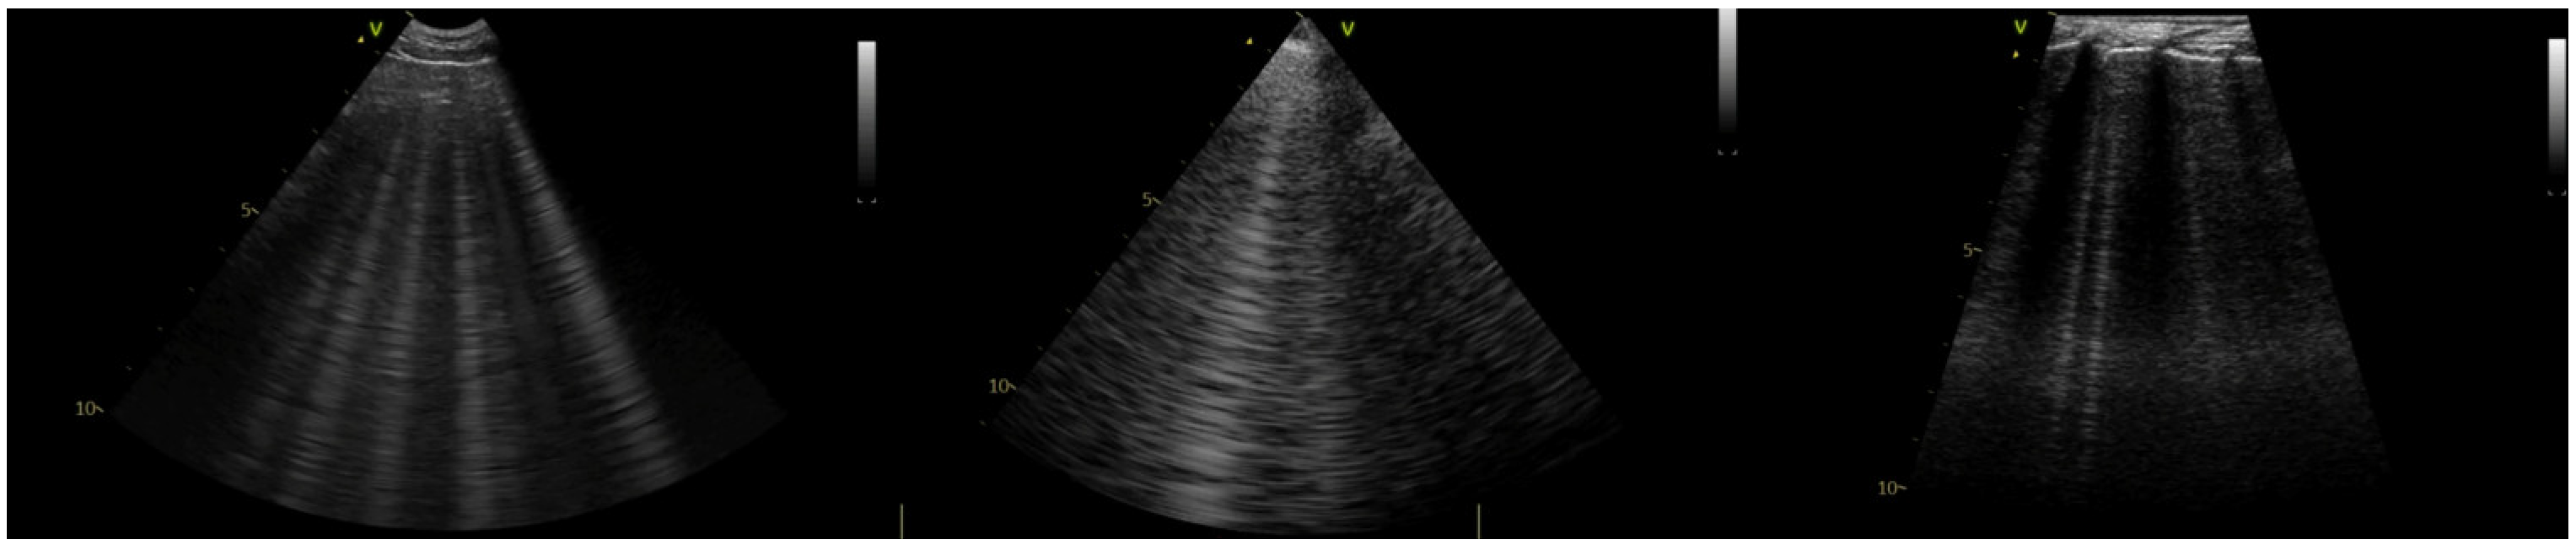

2.2. Lung Ultrasound Examination

The examination was performed following a predefined standardized approach by one of two experienced sonographers with over 5 years of experience in LUS (MG and KK). The LUS technique was performed according to a sliding protocol described elsewhere [,]. Briefly, a horizontal sliding technique with the transducer placed at three different vertical locations on each side of the thorax was utilized. The starting orientation of the probe is perpendicular to the ribs. The transducer is then slid along a dorsal line from cranial to caudal, rotated 90 degrees into a transverse plane (parallel to the ribs), and slid again from caudal to cranial direction along the same line. This process is repeated in the middle and ventral thirds of the hemithorax and then repeated on the contralateral hemithorax. All LUS exams were performed with a 3–8 MHz microconvex transducer, a 3–6 MHz phased array (PA) transducer, and a 6–12 MHz linear transducer, and cine-loops were recorded using a GE Vivid IQ ultrasound machine. The transducers were always held in the same position relative to the patient, perpendicular to the ribs. When a site positive for HVAs was identified with a microconvex transducer, 3–5 s cine-loops were recorded with imaging depth set at 8 to 10 cm. The operator fixed their hand on the lateral thoracic wall of the patient and then replaced the transducer without moving their hand. Using this technique, cine-loops were recorded for the same thoracic window with the PA transducer, followed by the linear transducer (Figure 1).

Figure 1. Still images from cine-loops recorded with three transducer types (from left to right): microconvex, PA, and linear.

The ultrasound settings were chosen based on previous publications [,], which have stated the need for a specific lung ultrasound preset to obtain images with the least impact of machine post-processing on naturally occurring artifacts. For this purpose, harmonics should be turned off, the frequency set to the lowest value for the transducer, persistence set to zero, the focal point set at the level of the pleural line, and time-gain compensation (TGC) increased at the distal (far) field of the screen. These settings were utilized in the current study, with the exception that the TGC was not increased in the far field; instead, the TGC was set to a mid-range level throughout to create a more uniform echogenicity between images and transducers, facilitating comparison by the evaluators [,,,,]. Cine-loops (n = 24) were stored for retrospective evaluation by two blinded reviewers.